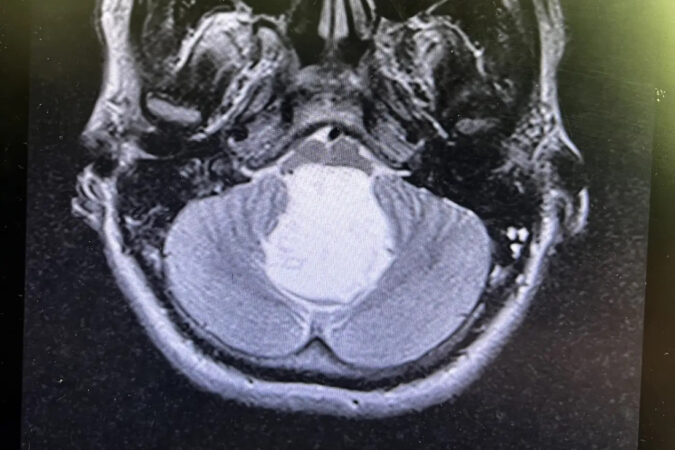

Молодой сибиряк к тому моменту с трудом мог ходить. А врачи, увидев снимки МРТ, не поверили, что перед ними живой человек — опухоль в его голове вплотную прилегла к дыхательному центру в мозге. Он могу умереть в любую секунду. Да и новообразование было весьма редкое — огромная перламутровая киста, которую выявляют у 3-9 человек на каждые 100 тысяч населения в год.